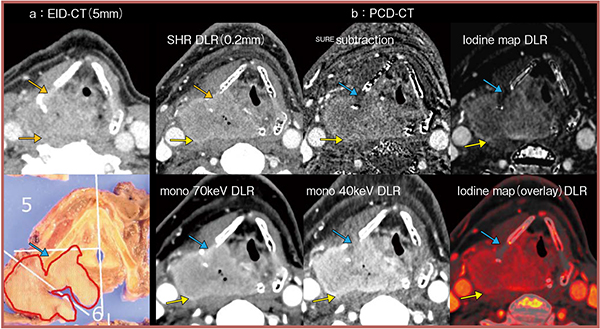

図3は実際の画像で,EID-CT(a)では軟骨および椎前筋への浸潤を否定できないが,PCD-CT(b)では高分解能に加え,一度の撮影でさまざまな種類の画像を取得し,差分画像やヨードマップによって軟骨浸潤を否定できる。また,virtual monochromatic image(VMI)の低keV画像ではヨードと軟部組織とのコントラストが向上するため,椎前筋浸潤は陰性であると評価可能であった。

図3 PCD-CTによる軟骨および椎前筋への浸潤の評価

→:EID-CTや120 kV画像では軟骨浸潤や椎前筋浸潤の評価が難しい。

→:非骨化軟骨へのヨード増強を認めず,軟骨浸潤陰性と判断可能

→:椎前筋との境界が明瞭で,浸潤なしと評価可能